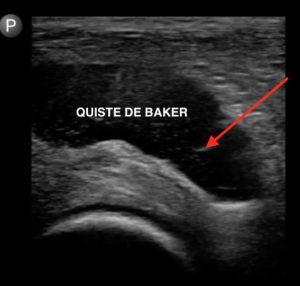

- Ecografía: La ecografía es una técnica que utiliza ondas sonoras para crear imágenes de los tejidos del cuerpo. Permite visualizar el quiste de Baker y evaluar su tamaño, forma y contenido líquido. Además, también puede ayudar a descartar otros problemas en la zona afectada.